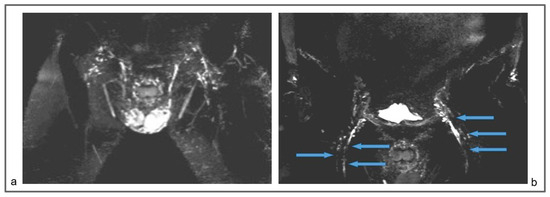

Figure 8.

Patient 3. (a) Preoperative non-contrast MR lymphography (a) (based on high-resolution heavily T2-weighted coronal sequences (turbo spin echo with repetition time 2870 ms, echo time 797 ms, field of view 380 × 380 mm, matrix 358 × 384, slice thickness 1 mm) and follow-up non-contrast MR lymphography (b,c) 1 year post-surgery. Follow-up (b,c) imaging shows the presence of new lymphatic vessels (blue arrows), not recognizable at the preoperative exam (a).